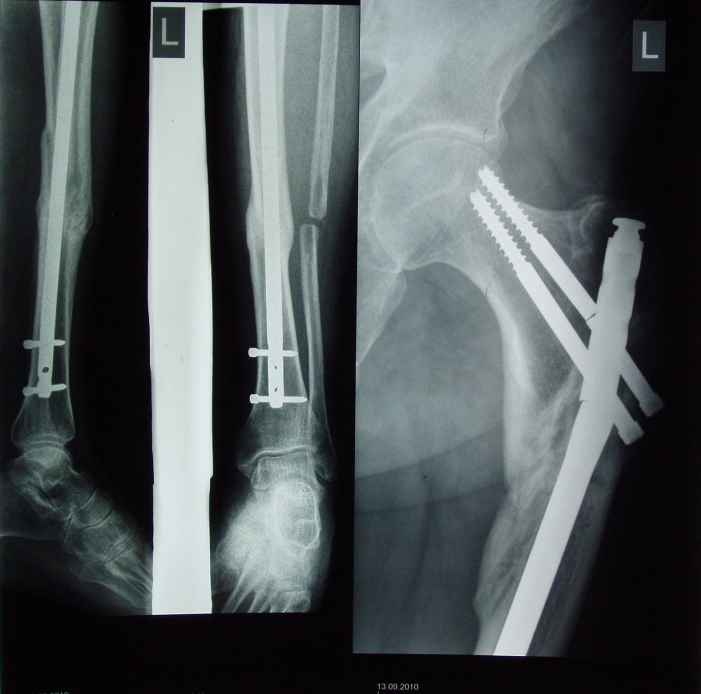

Доброго времени суток, уважаемые коллеги. Хочу представить вашему вниманию ситуацию в

которой мы оказалисти. 1,5 года назад данному пациенту было произведено штифтование

методом БИОС при переломах средней трети большеберцовой кости и верхней трети бедренной

кости левой нижней конечности.

В раннем послеоперационном периоде больной оказался вне нашего внимания,и через 6 месяцев

после синтеза была произведена резекция малоберцовой кости, туннелизация областей

переломов, динамизация стержней, компрессирование перелома большеберцовой кости с

помощью заглушки. В динамике больной активно пользовался конечностью.В области перелома

большеберцовой кости достигнуто сращение. В сентябре в области левого бедра больной

услышал хруст, обрасти внимание на боли при ходьбе в области перелома. При осмотре у больного

отмечено укорочение укорочение левой нижней конечности до 4 см. На рентгенограммах

определяется перелом винтов и верхней трети гвоздя, смещение в чрезвертельной области,

изменение оси бедра. Больному предстоит операция реостеосинтеза, уважаемые коллеги,

мнения докторов в выборе метода операции разошлись. DHS, перештифтование, PFN. Хочется

услышать ваши мнения. Заранее благодарим. К сожалению все снимки на данный момент

предоставить не можем.